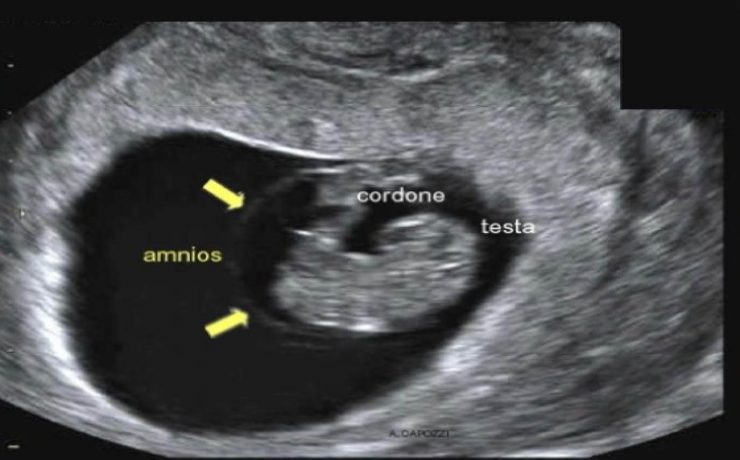

Patología fetal segundo trimestre

El RCIU constituye una de las mayores complicaciones del embarazo en. En incidencia de 3 a 10% en países desarrollados y 30% en países en vías de desarrollo. Recién nacidos con RCIU expuestos a riesgos de morbimortalidad neonatal por asfixia perinatal, encefalocele, hipoxia –isquémica, circulación fetal persistente, enterocolitis necrosante etc…